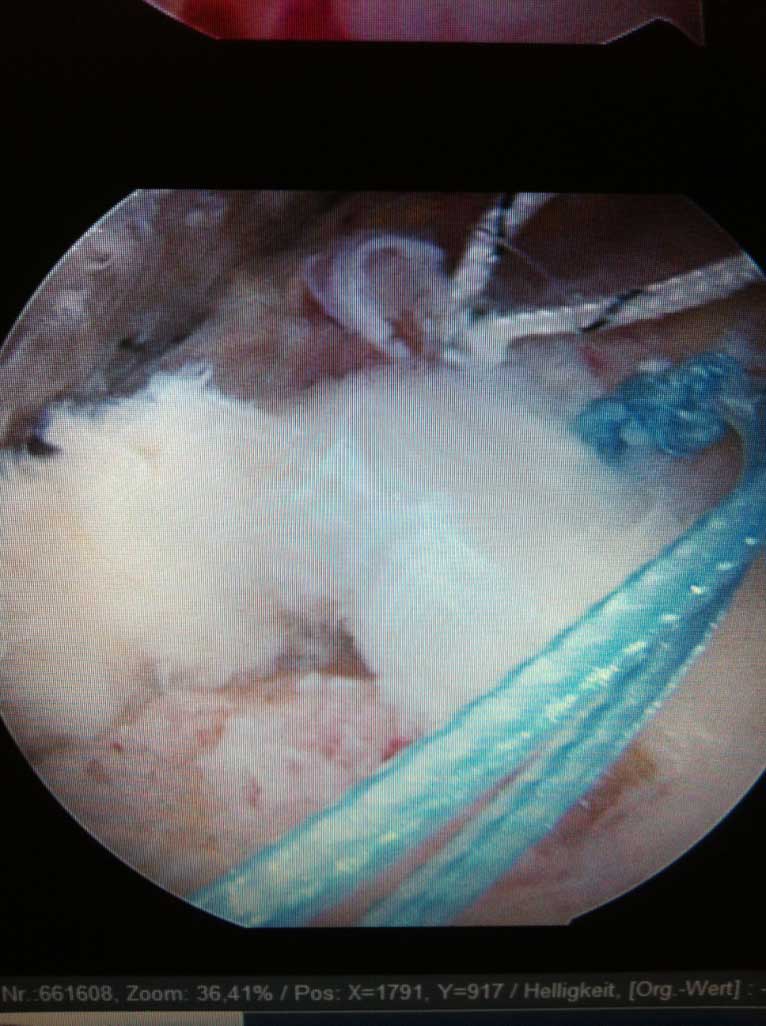

Je nach Alter, Verletzungsmuster, Anzahl der Luxationsereingnisse und weiteren Faktoren, wird eine schulterstabilisierende Operation indiziert und empfohlen. Diese führen wir ebenfalls ausschliesslich arthroskopisch

(Schüsselloch Operation) durch. Innerhalb von 15 - 30 min wird dabei der knorpelige Ring (s.g. Labrum) auf den knöchernen Pfannenrand mit speziellen Anker und Fäden wieder zurück befestigt.